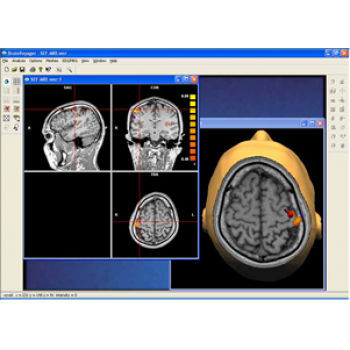

Visualization Tools

Parametric and non-parametric statistical maps may be superimposed both on the original functional scans as well as onto T1-weighted 2D or 3D anatomical reference scans. Time courses of selected regions-of-interest (ROIs) are available both in 2D and 3D representations. Statistical maps may be computed either in the 2D or 3D representation since structural as well as functional 4D data (space x time) are transformed into Talairach space. This allows you to compare activated brain regions across different experiments and across different subjects

Segmentation

Segmentation of tissue (e.g., isolating the brain, differentiating gray and white matter) is performed using region-growing methods, filter operations as well as the application of 3D templates. Using the mouse it is very easy to explore a 3D volume with superimposed pseudocolor-coded statistical maps in a four-window representation showing a sagittal, coronal, transversal and oblique section. Based on a (segmented) 3D data set a three-dimensional reconstruction of the subjects' head and brain can be calculated and displayed from any specified viewpoint using volume or surface rendering.

Surface Reconstruction

The surface reconstruction procedure starts with a sphere (recursively tesselated icosahedron) or a rectangle, which slowly wraps around a (segmented) volume data set. In order to avoid topological defects and to let the surface smoothly grow into deep sulci, a dynamic mesh algorithm was developed which automatically invents new polygons on the fly at places where they are needed. A reconstructed cortical surface may be inflated, cut interactively and slowly unfolded minimizing areal distortions. Statistical 3D maps may be superimposed on reconstructed, inflated or flattened cortex. Signal time courses may be invoked by simply pointing to any region of a visualized surface.